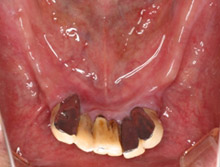

治療前のパノラマエックス線写真。歯がほとんど残っていませんし、残っている歯もほとんど使えません。

治療前口腔内。残っている下の前歯は重度歯周病で揺れています。審美と機能の改善を患者さんは希望されました。

術前の上顎

術前の下顎